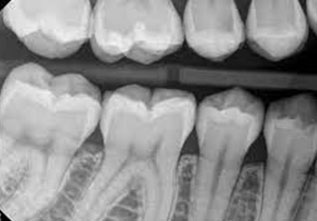

BITEWING RADIOGRAPHS

Bitewing radiographs are indicated primarily to detect or monitor hidden caries in the interdental tooth surfaces. Very useful for a dentist, as the proximal surfaces of the teeth cannot be visually examined or clinically accessible with dental explorers.